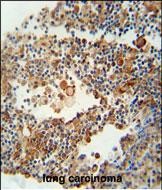

- OR9Q1 antibody (C-term) (Cat. #P30870) immunohistochemistry analysis in formalin fixed and paraffin embedded human lung carcinoma followed by peroxidase conjugation of the secondary antibody and DAB staining. This data demonstrates the use of the OR9Q1 antibody (C-term) for immunohistochemistry. Clinical relevance has not been evaluated.